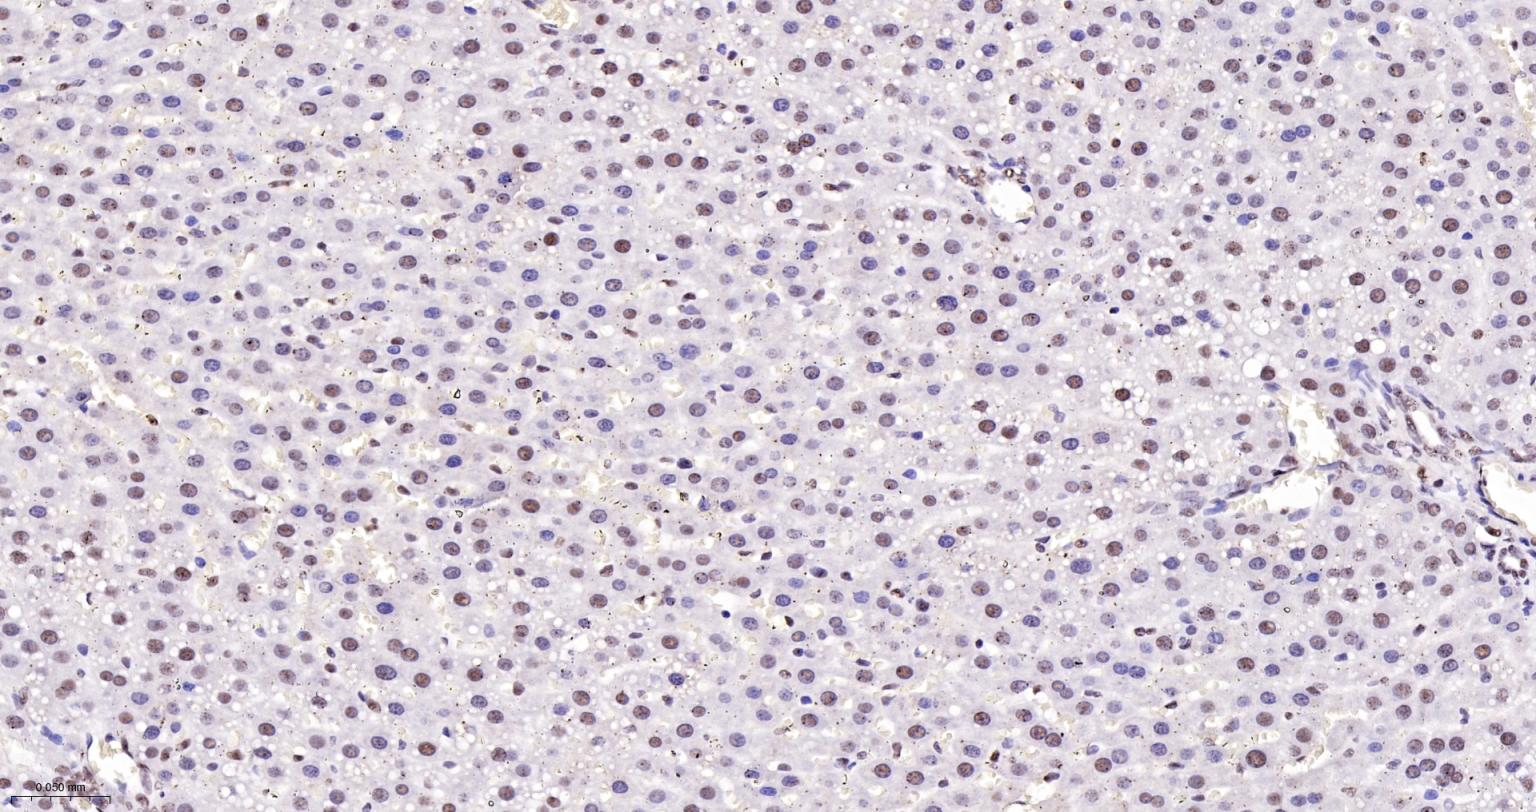

Paraformaldehyde-fixed, paraffin embedded Rat Liver; Antigen retrieval by boiling in sodium citrate buffer (pH6.0) for 15 min; The section was incubated with TCEA1 Monoclonal Antibody, Unconjugated (bsm-62989R) at 1:200 overnight at 4°C, followed by conjugation to the bs-0295G-HRP and DAB (C-0010) staining.

Paraformaldehyde-fixed, paraffin embedded Mouse Liver; Antigen retrieval by boiling in sodium citrate buffer (pH6.0) for 15 min; The section was incubated with TCEA1 Monoclonal Antibody, Unconjugated (bsm-62989R) at 1:200 overnight at 4°C, followed by conjugation to the bs-0295G-HRP and DAB (C-0010) staining.